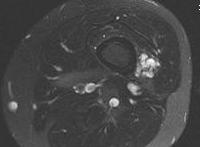

MRI

Exceedingly bright signal due to the high fluid content of the lesion